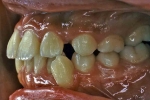

マルチブラケット終了時